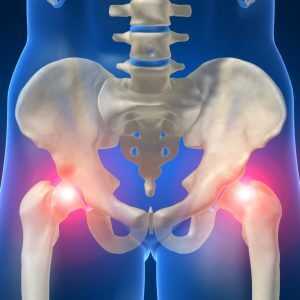

Эндопротезирование тазобедренного сустава

Тазобедренный сустав является самым крупным по размерам суставом в теле человека. Эта система соединяет тазовый скелет с бедренной костью таким способом, благодаря которому нижняя конечность является подвижной в разных плоскостях.

Во время ходьбы на него воздействует давление всей верхней части туловища, то есть ежедневно сустав подвергается значительным нагрузкам. Как и любое системное сложное образование в теле человека, тазобедренный суставной аппарат в течение жизни человека может подвергаться разнообразным травмам и патологиям: они могут быть связаны с врождёнными аномалиями развития, с неудачным механическим воздействием или наличием воспалительных процессов и некоторых заболеваний.

В чём суть процедуры эндопротезирования, зачем она назначается

Различные дегенеративно-дистрофические поражения суставного аппарата могут сформироваться у человека на любом этапе его жизни. Их основная опасность в том, что, во-первых, со временем они только прогрессируют, а во-вторых, если вовремя не оказать врачебную помощь, человек может полностью лишиться возможности самостоятельно передвигаться, и окажется прикованным к постели. Болезни и патологии тзб сустава могут быть причиной формирования инвалидности поражённого.

Особенно часто встречается деформирующий артроз, при котором прогрессирующий патологический процесс постепенно видоизменяет форму суставных элементов, деформируя их, в результате чего человек теряет подвижность конечности и постоянно чувствует боль.

Консервативное лечение в таких случаях обычно неэффективно - оно может лишь замедлить процесс, причём только на ранних стадиях. Если болезнь запущена, лечащий врач принимает решение о проведении эндопротезирования.

Что это такое - эндопротезирование тазобедренного сустава? В процессе операции хирург осуществляет физическое извлечение поражённых элементов суставного аппарата, и заменяет их на искусственные протезы. Процедура проводится для достижения нескольких целей - устранения болей в суставе, улучшения его подвижности, возврата пациента к привычному образу жизни, возвращения ему способности ходить и двигаться.